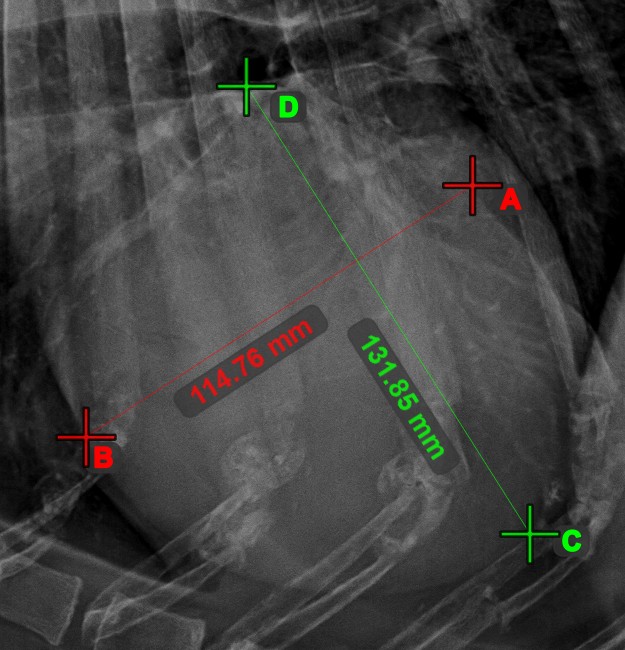

Line Measurement¶

Select the Line Measurement

tool and assign it to one of the available mouse buttons. Place the start and end points on the scene or select them from already existing points on the image. The distance between the two points will be automatically

calculated by using the default calibration data, or the recalibrated data by the length calibration measurement.

Measurement Point¶

Measurement Point

tool. Each point is assigned with a letter for better identification.Select/Move Item

tool. Select the point by using the assigned mouse button of the tool, and then move it freely anywhere on the image.